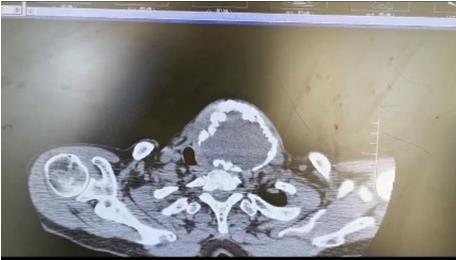

患者朱女士,68岁,颈部包块呈进行性增大50年,来院后彩超及CT提示左侧甲状腺肿瘤已经超过10公分并边缘钙化,气管移位较明显,肿瘤较大属于罕见,不仅给患者造成心理阴影,还影响了正常生活,偶有憋闷不适,进食较大食物感哽咽不适。流动医院下乡义诊时,发现包块已经很大了,影响到颈部的活动及饮食。医生与患者及家属沟通讲解病情,表示我们三甲医院能治疗。最后患者及家属抱着试一试的态度来到延安大学咸阳医院。

因逐渐长大的颈部严重影响饮食及活动,长达50年的折磨,患者身体很瘦、体质差。甲状腺肿瘤,瘤体大,手术创面较大,损伤喉返神经及甲状旁腺风险高,术后可能出现声音嘶哑及低钙抽搐等严重并发症。同时瘤体长期对气管的压迫,致术后可能出现气管软化而发生致命性并发症。

经过普外二科赵建辉主治医师及他们的团队与麻醉科讨论研究,认真分析颈部的解剖结构。确定最优手术方案。于2022年1月14日上午在全身麻醉下行左侧甲状腺大部分切除+喉返神经探查术,手术历时1.5小时,顺利结束,出血量较少,术中快速冰冻为结节性甲状腺肿。考虑到创面较大,术中放一条引流创腔管,较好的保护了喉返喉上神经及甲状旁腺,手术成功。